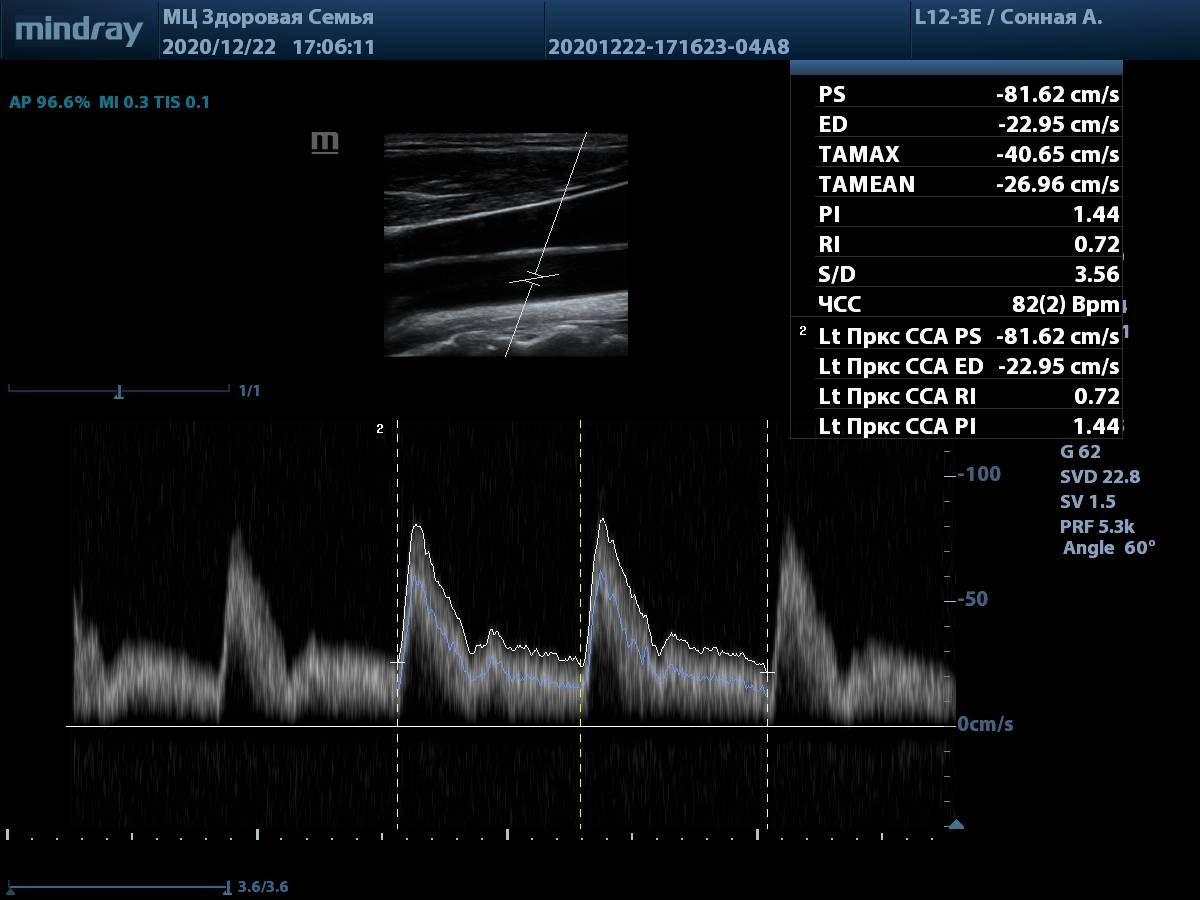

Визуализации поджелудочной железы

9. Общая сонная артерия, PW-допплер. Автоматическая трассировка игнорирует мелкие артефакты, четко повторяя спектр, а также использует несколько комплексов для снижения погрешности. Для отправки результата в отчет достаточно выбрать параметр в меню измерений.

Общая сонная артерия, автотрассировка